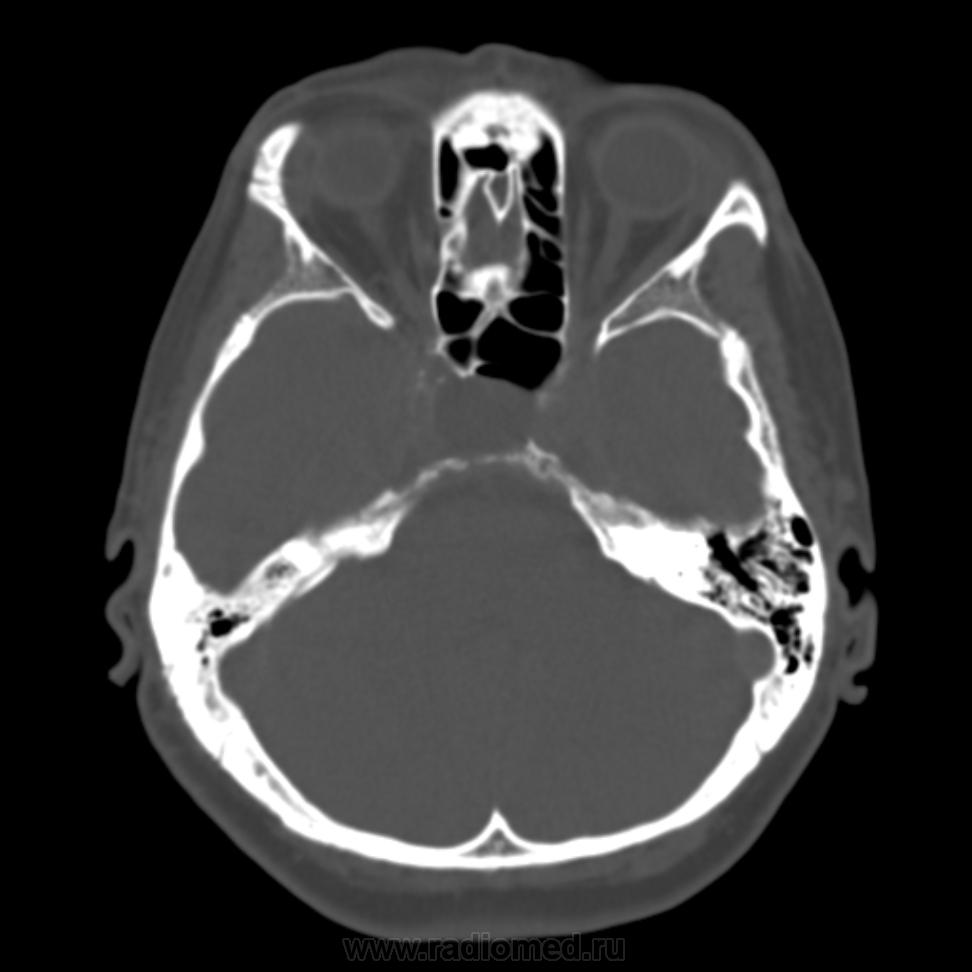

образование средней черепной ямки справа, образование турецкого седла?

женщина. 58 лет. жалобы на головные боли. саму пациентку не видел. в карте о вмешательствах на черепе ничего нет. что скажете по данным снимкам?

Да.